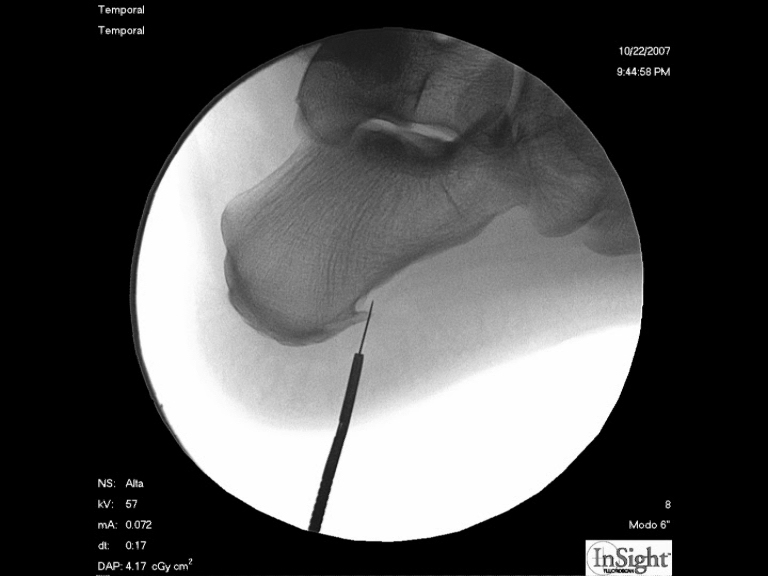

Foto 1

En la radiografía marcamos el espolón que surge de la planta del hueso calcáneo, este espolón no es el motivo del dolor, si no el resultado de la inflamación crónica de la fascia plantar que se ancla en el punto donde surge el “pico” del hueso, y que es el verdadero responsable del dolor. |